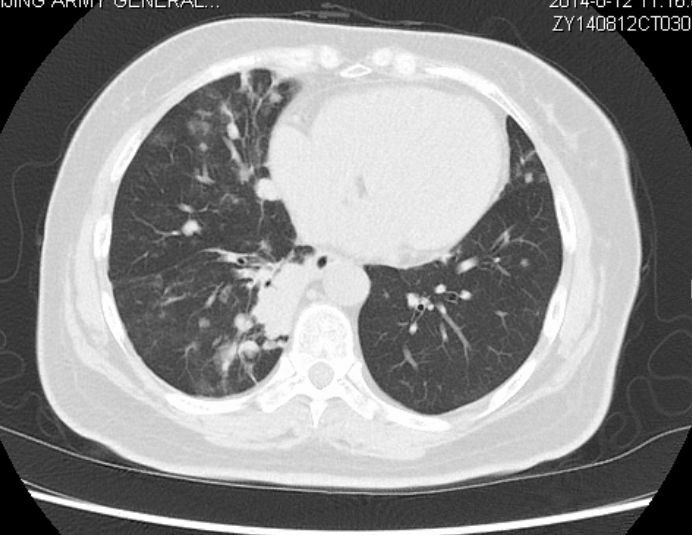

以下是第50个月的时候复查:

与两年前对比,病灶有所增大,但未影响肺功能,老太太总体状态很不错!

该患者在确诊时已经属于肺癌晚期伴有多发转移,最后一次随访时,已经带瘤生存50个月。